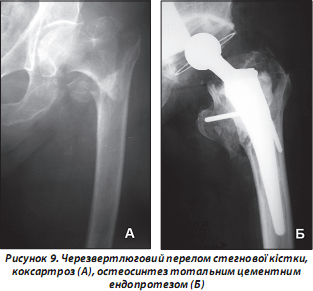

При деяких типах медіальних переломів (Garden 4), незрощеннях шийки стегнової кістки, переломах на фоні деформуючого коксартрозу ризик виникнення ускладнень та незадовільних результатів, отриманих за переліченими методиками оперативного лікування, надмірно високий. Втрачається доцільність та раціональність виконання металоостеосинтезу.

У таких випадках перевагу віддають первинному цементному тотальному ендопротезуванню (рис. 9), що за ступенем травматичності та тривалості операції наближене до остеосинтезу динамічним стегновим гвинтом (DHS), проксимальним інтрамедулярним стегновим стрижнем (Proximal femoral nail (PFN) або гамма-цвяхом (Gamma nail).

Суттєва перевага методу полягає в ранній (на наступний день після операції) активізації хворих. Водночас заміна суглоба на штучний вже в ранні терміни (протягом двох тижнів) дозволяє здійснювати дозоване, а за два місяці — і повне навантаження кінцівки.